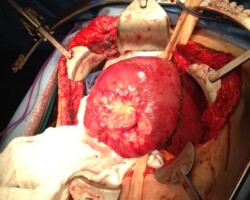

Resection of large retroperitoneal sarcoma including right and transverse colectomy and right hepatectomy